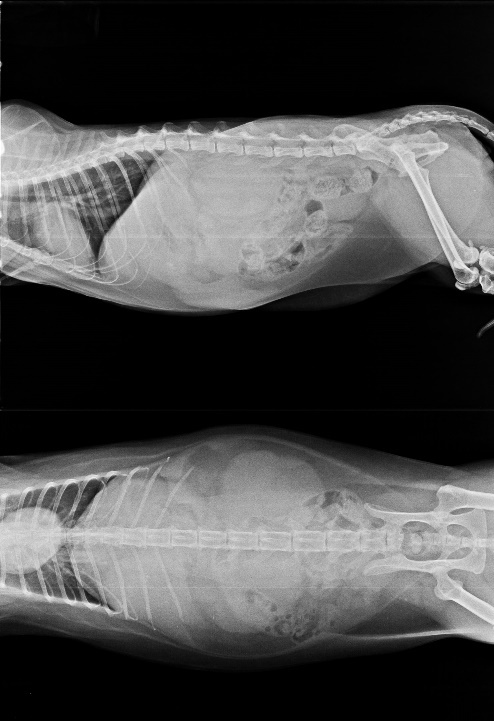

五月中旬憨面坐姿和臥姿感覺腹腔很不舒服

回診檢查腎臟有浸潤的現象,懷疑可能有轉移

腎指數偏高體重一直下降

照片使用的是紀錄